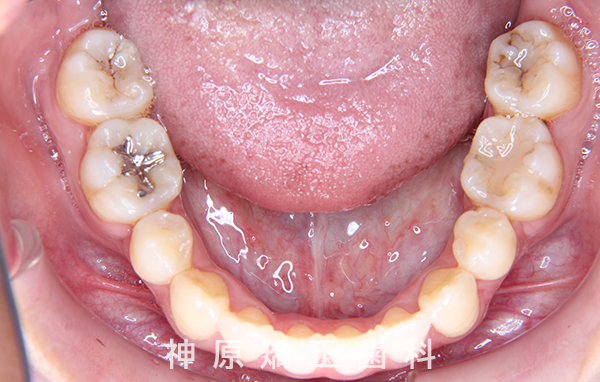

治療終了

治療前と治療後